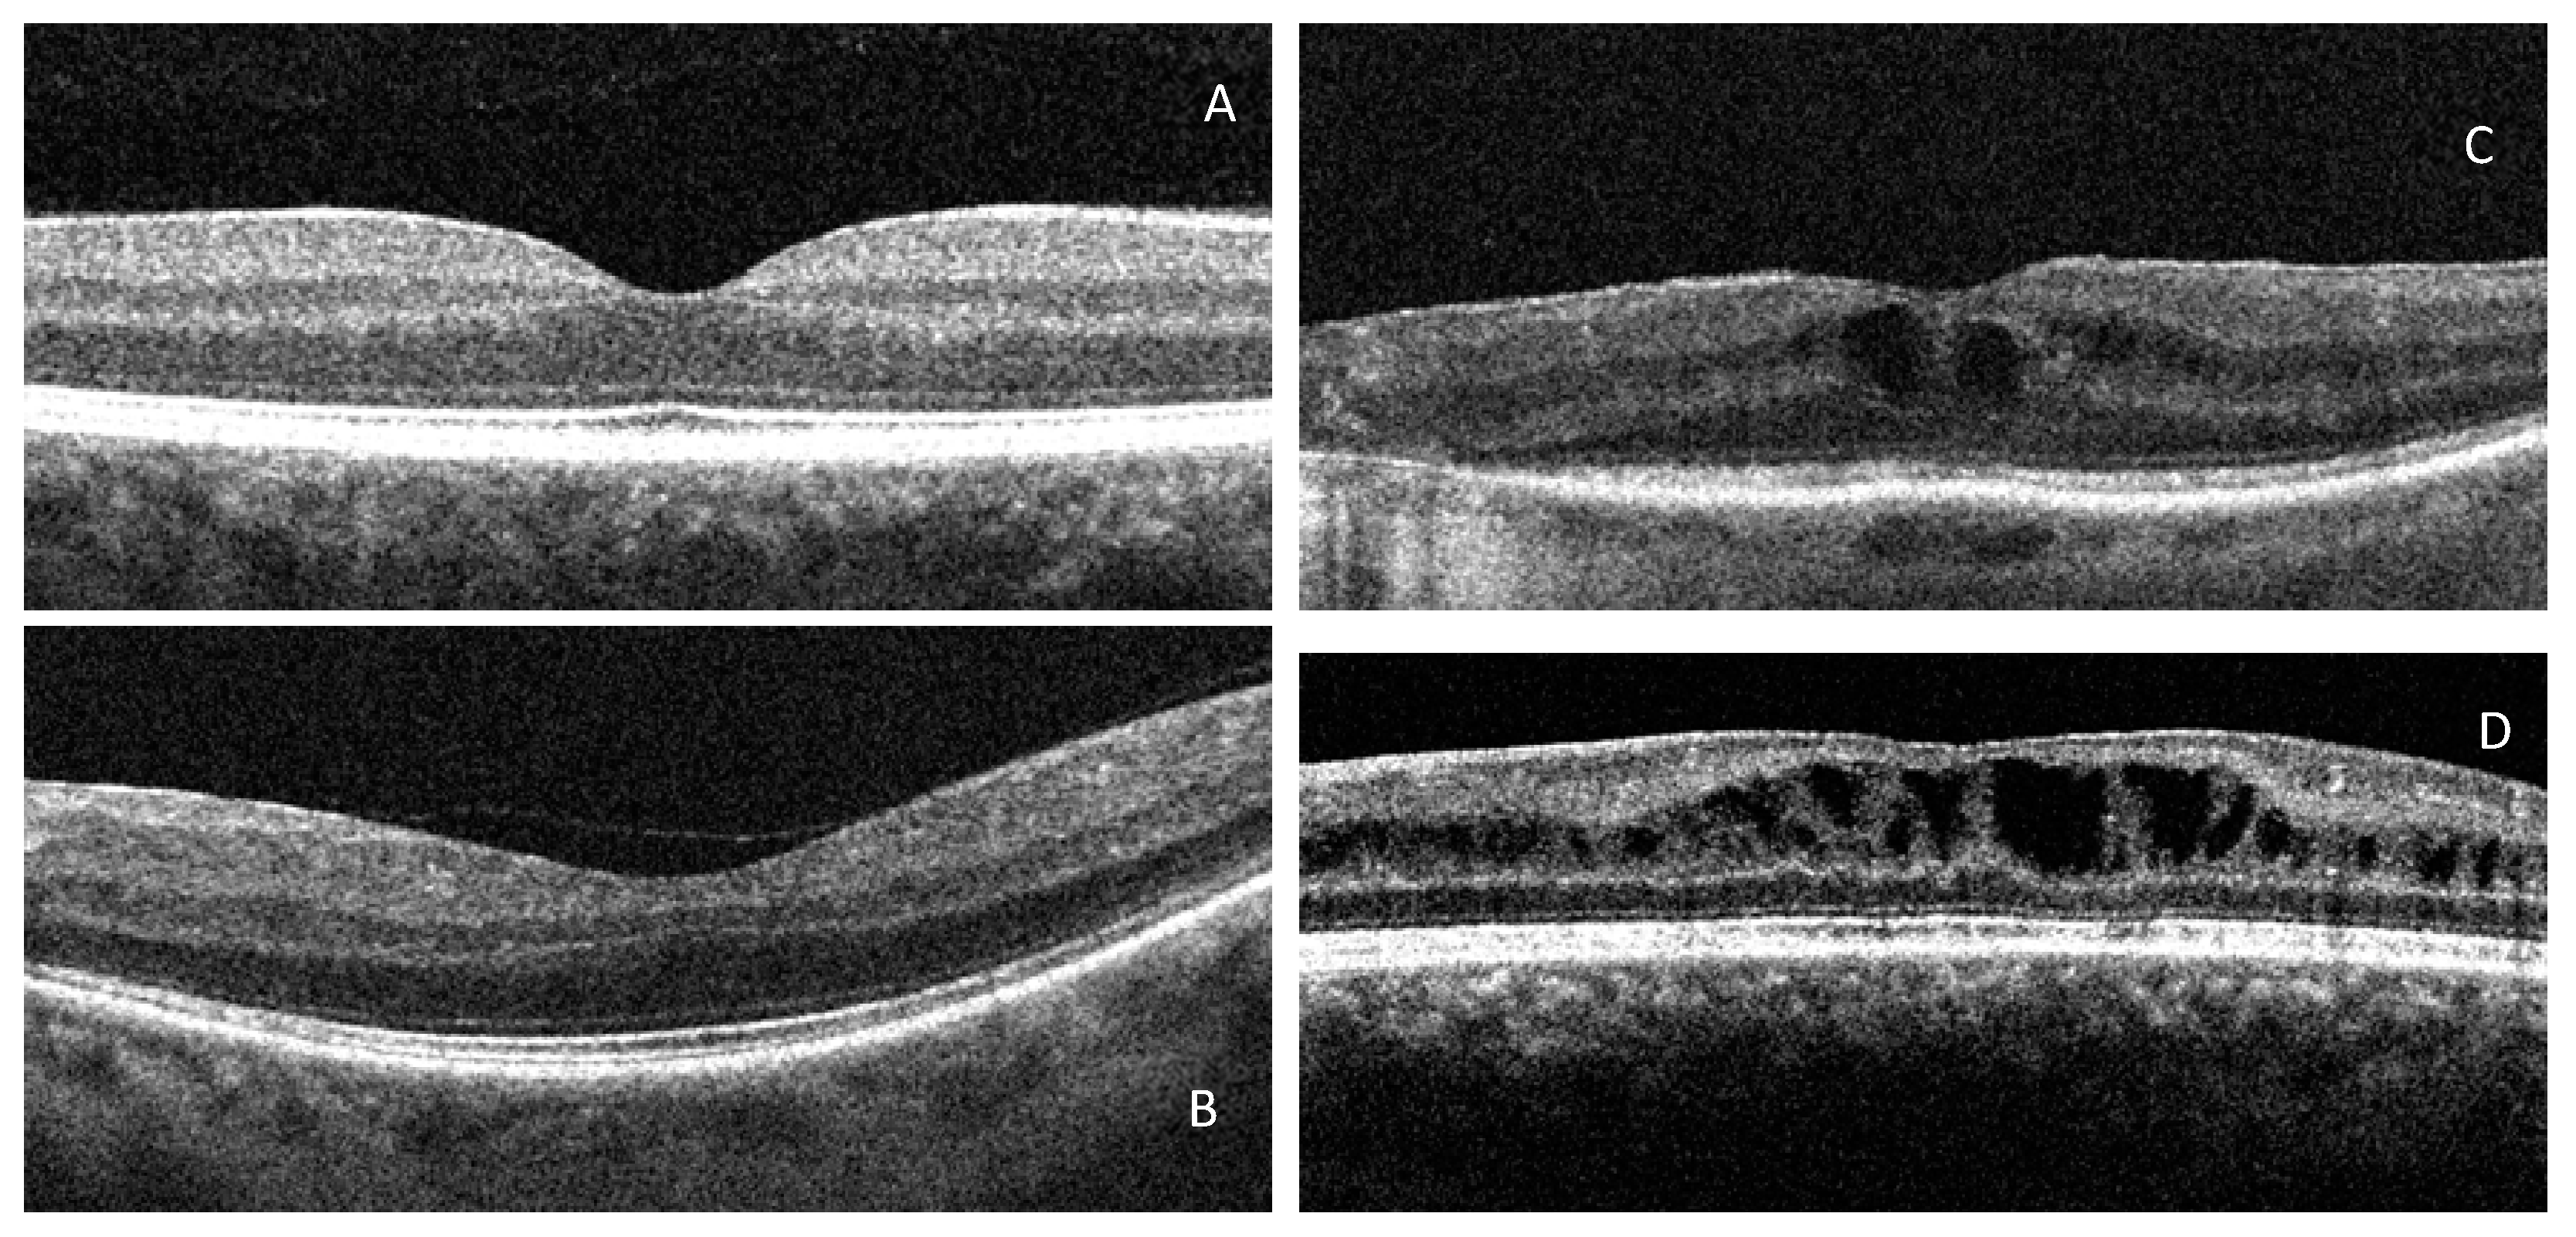

- Furthermore, our findings suggest that antioxidant supplements may improve morphological damage (CMT). Indeed, as reported in the literature, ROS promotes breakdown of the blood–retinal barrier and alters retinal blood flow by modulating the production of vasoactive factors, also upregulating the retinal expression of VEGF and adhesion molecules as ICAM-1 [31,32,33,34,35]. This cascade of molecular events causes leakage of fluids into the surrounding tissue, which initially accumulate within Müller cells. These morphological alterations may precede the appearance of CSME, they are quantifiable by OCT scans with CMT measurement, and they define the DRT pattern [4,8,11,15,36].